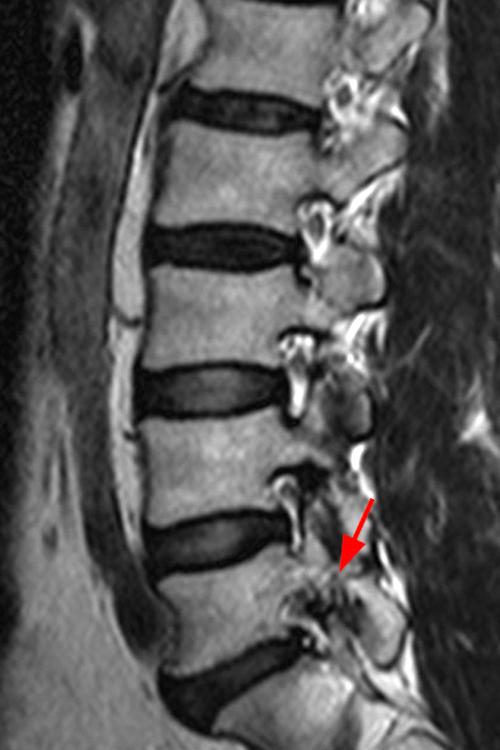

Case 1: 14-year-old female with back pain after a car accident. Axial T2-weighted (1A) and sagittal STIR (1B) images are provided. What are the findings? What is your diagnosis?

Case 1: T2-weighted axial (3A) and sagittal STIR (3B) sequences show marked cortical T2/STIR hyperintensity in the left pedicle of L5 surrounding a hypointense line (arrows) which begins at the inferior/medial margin of the pedicle and nearly completely traverses the pedicle.

Case 1: Acute left-sided pediculolysis